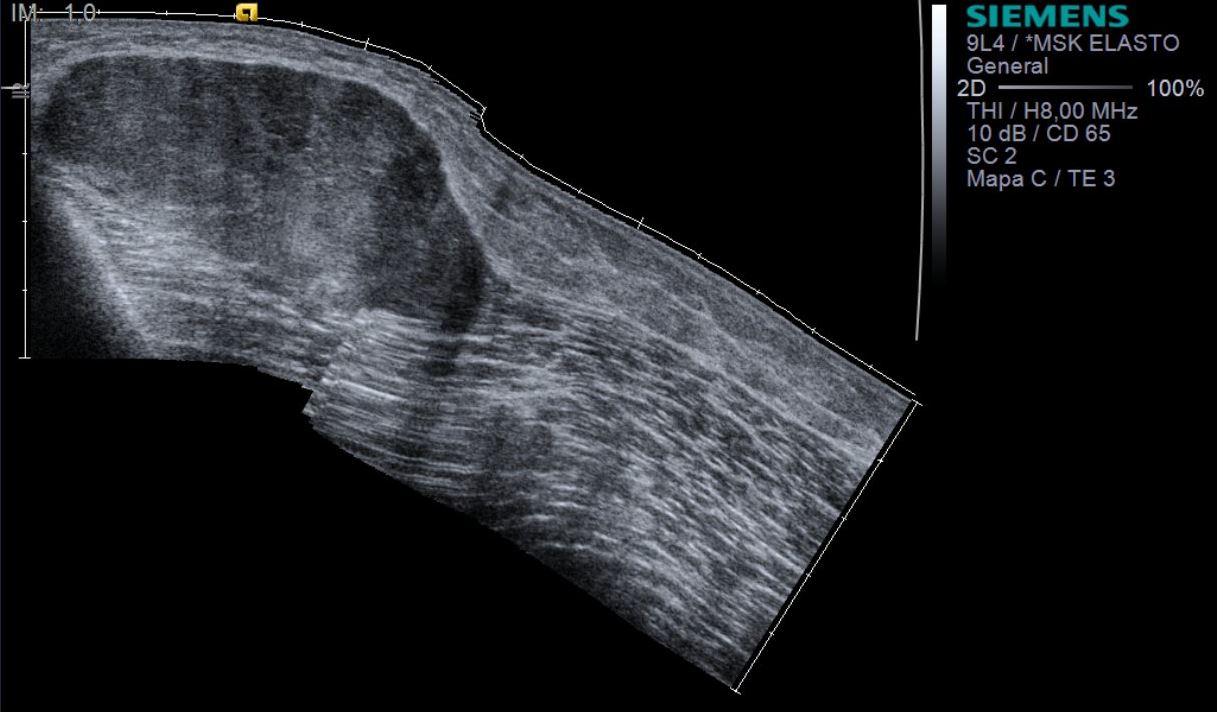

Ecografia de muslo derecho, modo B panorámico